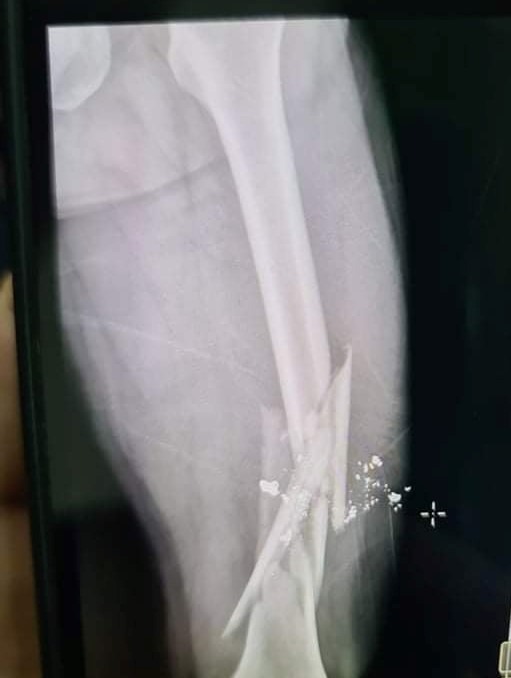

14/01/2022 18:08Người đàn ông bắn gãy xương đùi bạn nhậu để trả thù

Sáng nay ngày 14/1, theo thông tin chia sẻ từ lãnh đạo phường Hưng Trí, thị xã Kỳ Anh (tỉnh Hà Tĩnh), Công an thị xã Kỳ Anh đang tiến hành điều tra để xử lý vụ bắn nhau khiến 1 công dân của địa phương bị trọng thương trên địa bàn phường.

Trước đó, khoảng 12h trưa 12/1, một nhóm người đến ăn nhậu tại một nhà hàng tại phường Hưng Trí. Trong nhóm này có anh Phan Công Hoà (SN 1981, trú tại huyện Kỳ Anh) và anh Nguyễn Trường Giang (SN 1977, trú thị xã Kỳ Anh). Do bất đồng quan điểm nên giữa Hòa và Giang đã xảy ra mâu thuẫn dẫn đến xô xát. Quá trình xô xát, Giang có đấm vào miệng Hoà, thấy vậy nên mọi người lao vào can ngăn.

Sau chầu nhậu, cả nhóm ra khỏi quán rồi đứng lại tiếp tục nói chuyện. Lúc này, vì còn căm tức do bị đánh, Hòa đã bất ngờ lấy súng bắn bạn nhậu gãy xương đùi. Nạn nhân sau đó được mọi người đưa đến bệnh viện cấp cứu, đồng thời báo cơ quan chức năng.